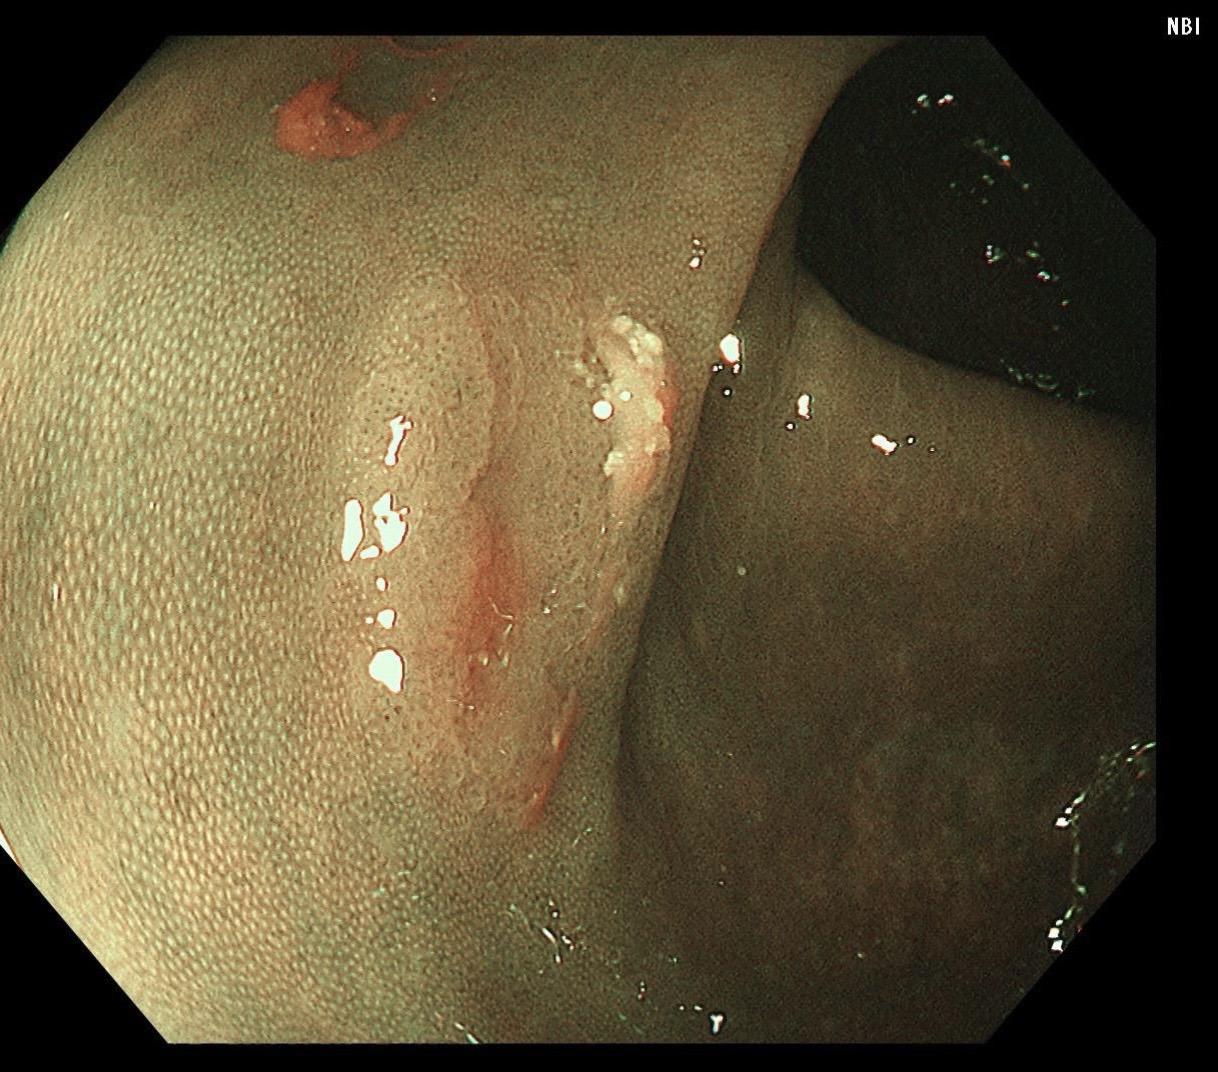

结肠SSL 醋酸染色。染色效果不亚于靛胭脂,结合NBI,Near focus观察表面结构非常OK,下次让护士长买大桶装的,1桶6块9,可以喷一年,哈哈……

结肠SSL 醋酸染色。染色效果不亚于靛胭脂,结合NBI,Near fo...